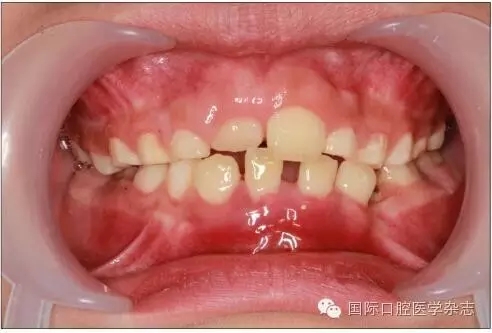

個(gè)別牙先天缺失常常造成牙列異常間隙,多數(shù)牙先天缺失會(huì)影響咀嚼功能和牙列形態(tài),嚴(yán)重者影響面容和美觀。牙齒的形態(tài)異常,如融合牙等會(huì)使牙弓大小、形態(tài)及咬合關(guān)系發(fā)生異常。乳牙滯留是指繼承恒牙已經(jīng)萌出,未能按時(shí)脫落的乳牙。乳牙牙根未吸收或非典型性吸收可導(dǎo)致恒牙萌出方向改變、位置異常,常見于下頜乳中切牙滯留,恒中切牙于舌側(cè)出齦,呈現(xiàn)“雙排牙”現(xiàn)象(圖5)。上頜牙齒在滯留乳牙腭側(cè)出齦則可能形成反(圖6)。

圖5 上頜前牙區(qū)多生牙導(dǎo)致上頜中切牙間隙,右上中切牙扭轉(zhuǎn)

Fig 5 Supernumerary teethin the area of maxillary anterior teeth caused incisor gap, reversed rightupper incisor